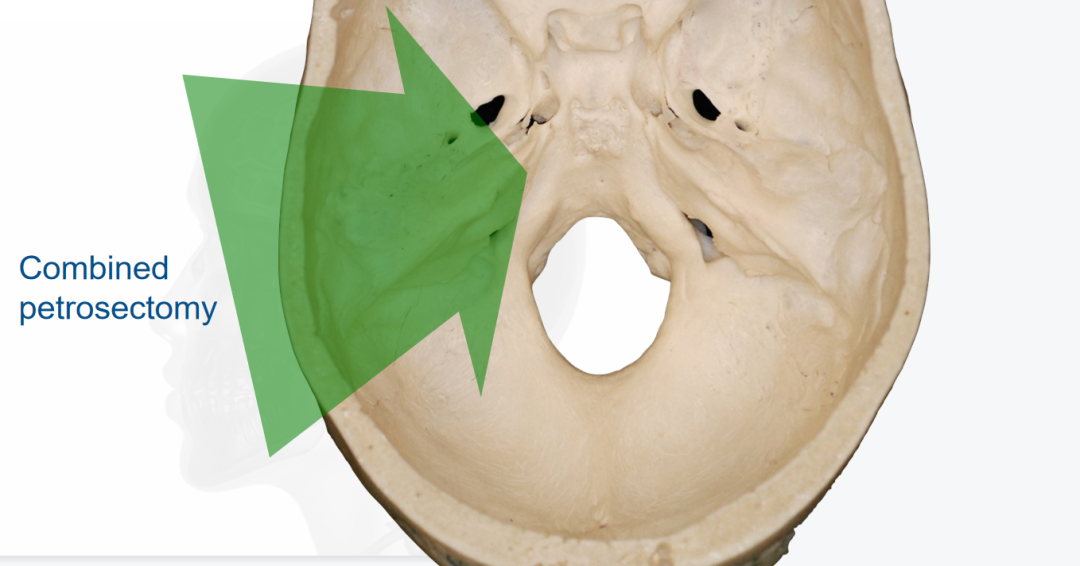

第三步是联合岩骨入路:这是福洛里希教授的核心手术策略——将岩前入路与岩后入路联合实施,同时配合颞顶枕开颅,从多角度多方向逼近肿瘤。这一入路方式的最大优势在于,能够在相对短的手术距离内为岩斜区提供宽阔的操作视野,同时将对脑组织的牵拉损伤降至最低。福洛里希教授曾于2019年在《Acta Neurochirurgica》杂志发表专题论文,系统详解了这一入路的每个关键操作步骤——这已不仅仅是一台手术方案,而是一套经过系统论证与长期实践检验的颅底手术理念体系。